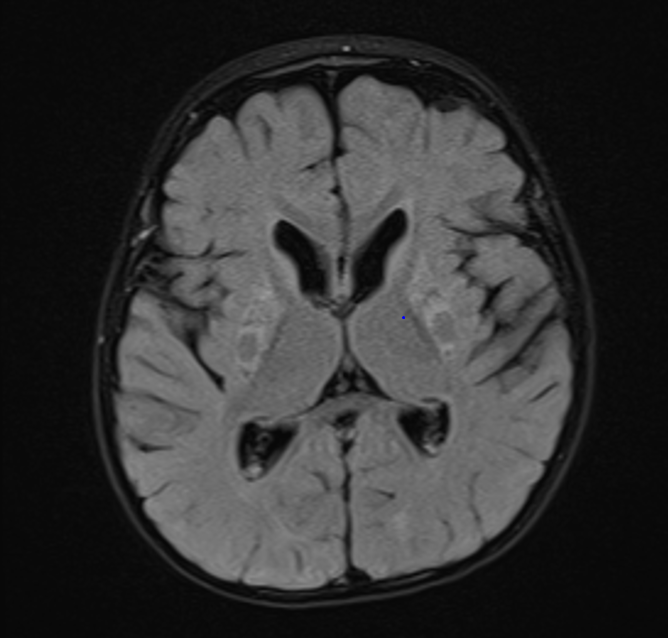

The putaminal eye: A highly characteristic imaging feature of MEGDEL syndrome

Inspired by a patient. Images obtained at 19 months. T2 above and FLAIR below.